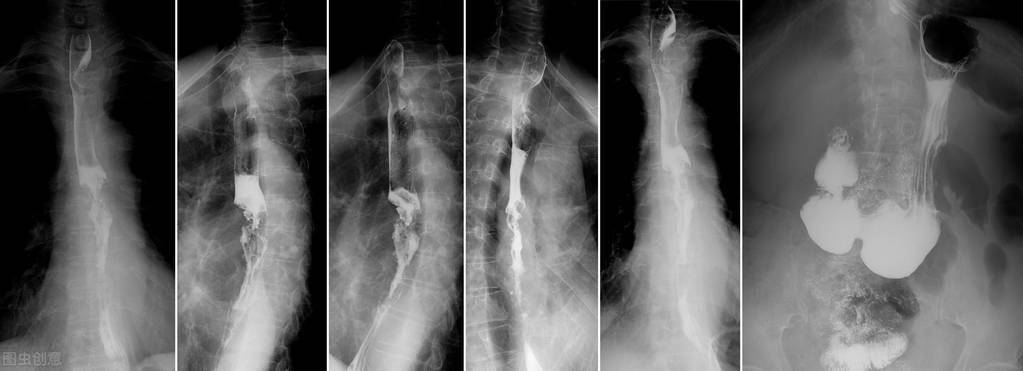

3、食管吞钡X线检查。对于比较典型的反流性食管炎,食管吞钡X线一般能诊断。当然,对于部分反流性食管炎,吞钡检查可能无法明确诊断,但它可以排除食管癌等其他食管疾病,同时相对于胃镜检查,它更加简单易行,对病人造成的痛苦也小,这是它的优势,所以对于部分患者可以作为筛查使用。